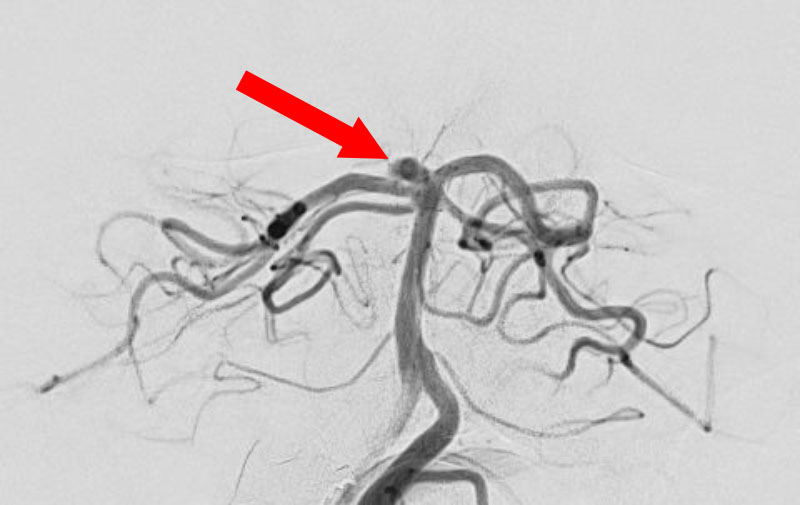

No.1596 手術後